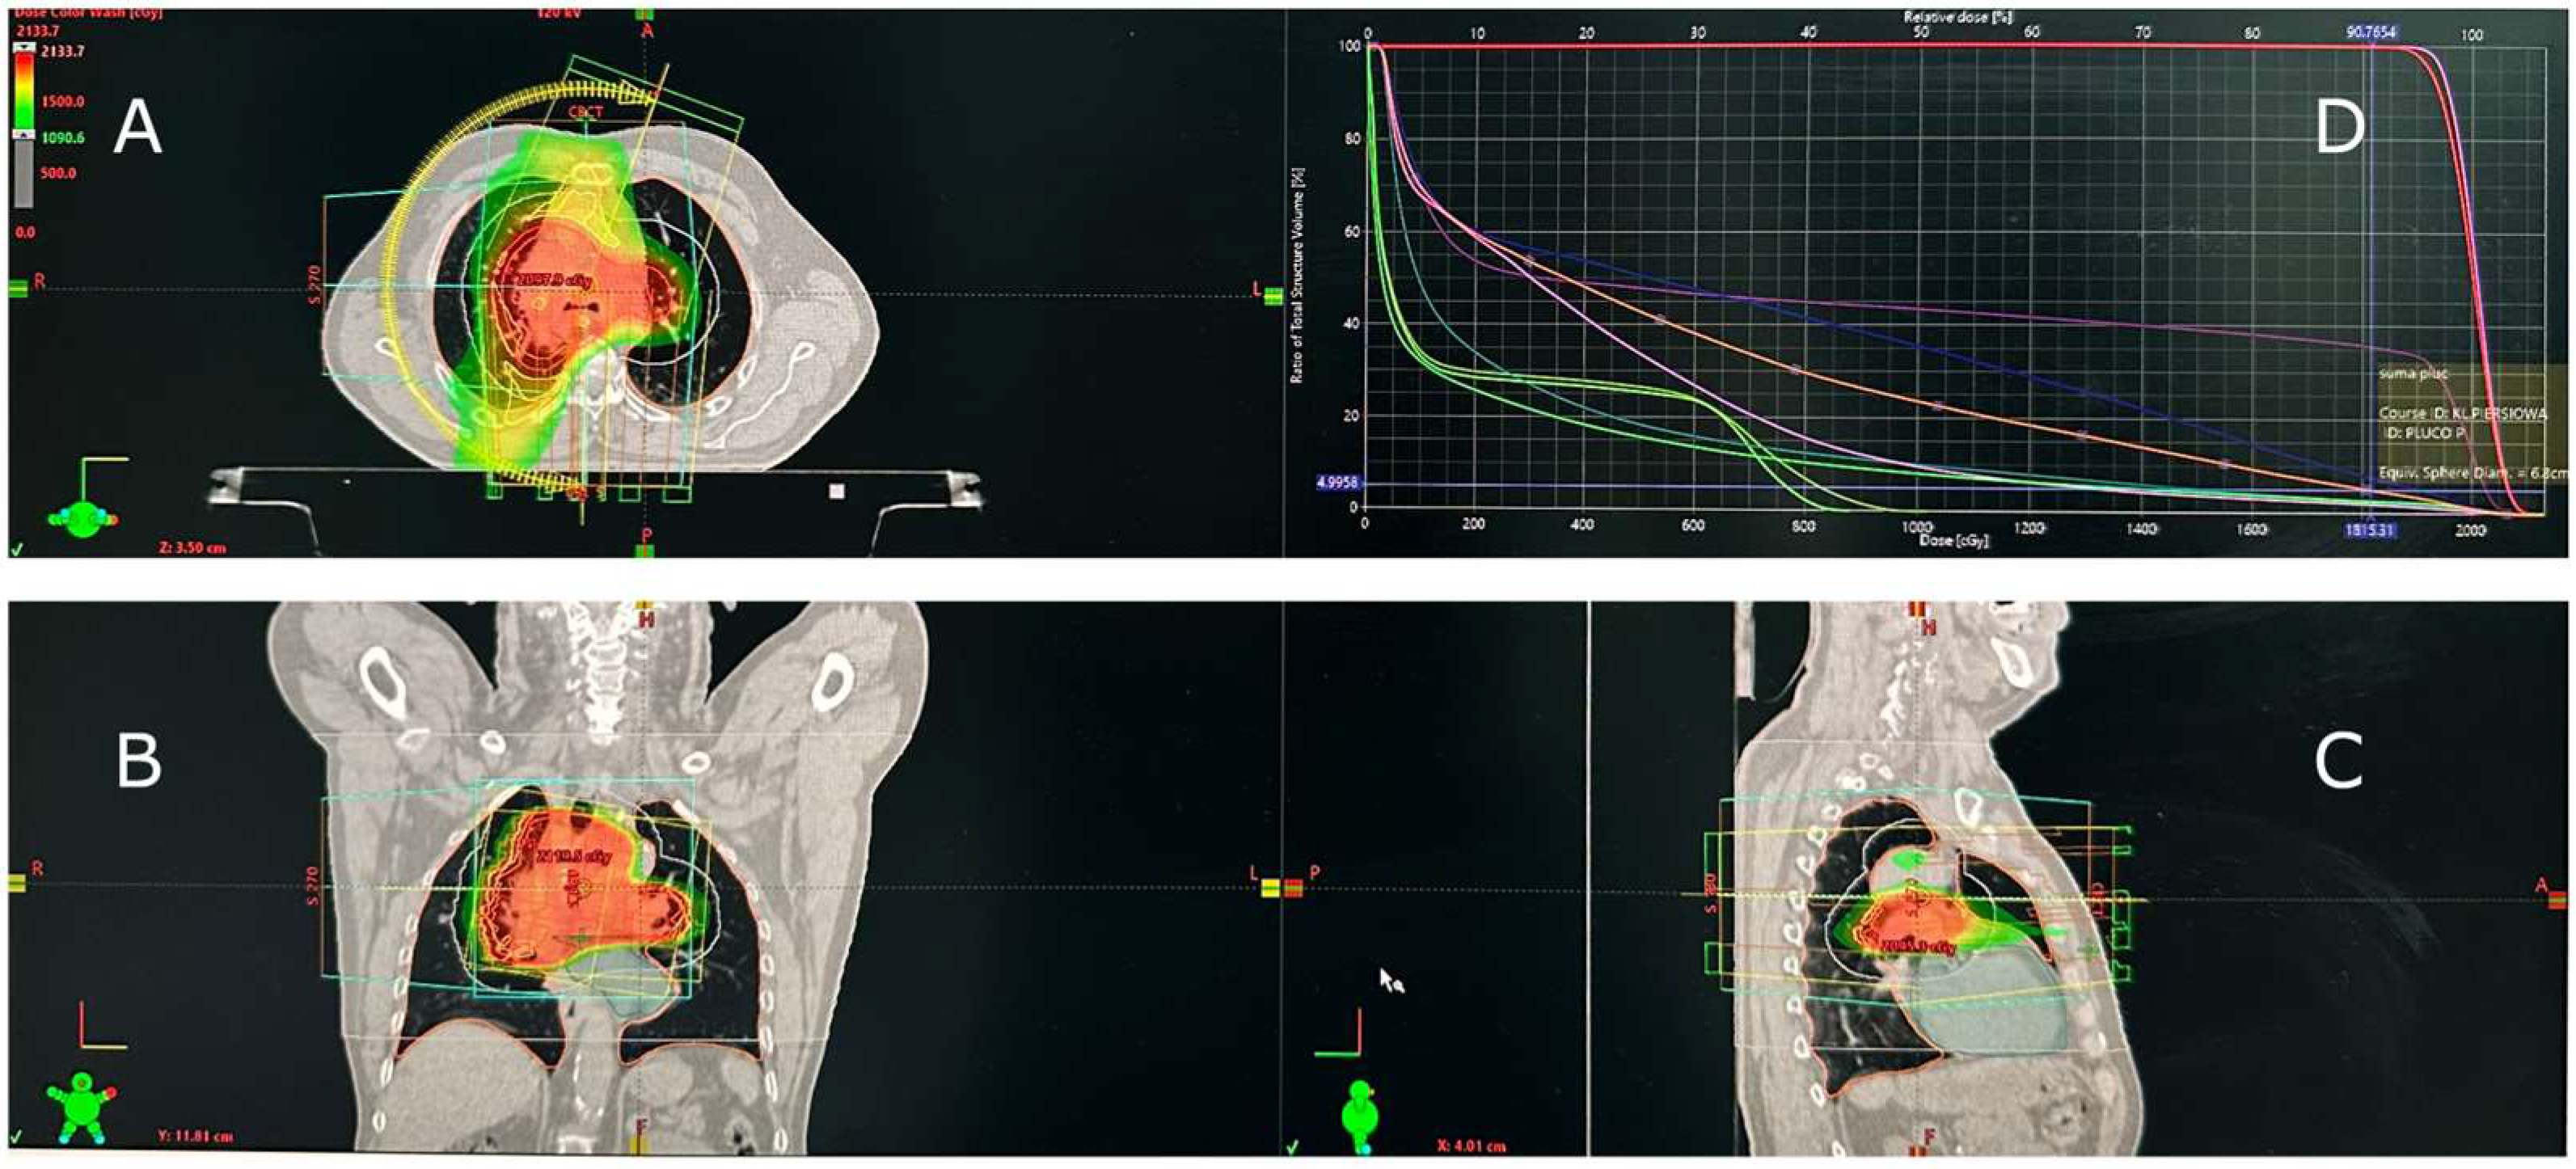

2. Case Presentation